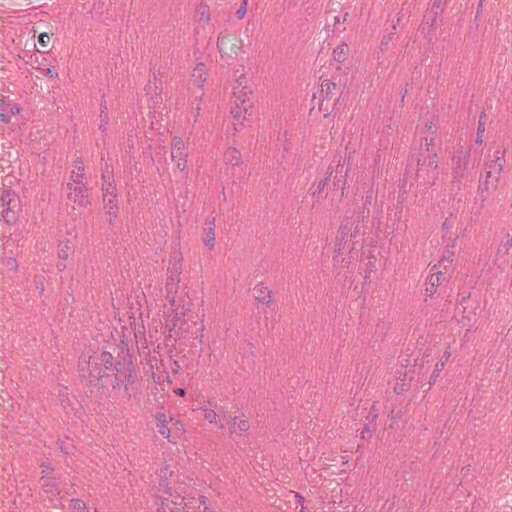

The tissue section shows elongated, spindle-shaped cells with elongated nuclei, typical of smooth muscle cells or fibroblasts, embedded in eosinophilic collagen-rich matrix. The disorganized arrangement and variable cellularity suggest a possible reactive or reparative process, possibly benign myofibroblastic or fibroblastic proliferation, in lung connective tissue. The uniformity in cell size and shape indicates no signs of malignancy. Possible diagnoses include leiomyoma or chronic fibrosis or indicating a well-aligned, myofibroblasticblastic proliferation. There's a benign proliferation of small, dark-staining nuclei suggesting inflammatory cell components or other cells, indicating a well-organized structure. The morphology maintains no evidence of malignancy or tissue disruption,isive of a reactive, active pathological change, possibly idiopath of interstitial lung disease, such as fibrosis.

The image displays well-differentiated smooth muscle tissue with spindle-shaped cells in interlacing fascicles and elongated nuclei. The pink-staining cytoplasm indicates eosinophilic filaments. Moderate collagenous extracellular matrix surrounds the cells. There are no signs of inflammation or necrosis, suggesting a sp muscle structure, from the stomach's muscularis propria of the stomach. No hepatocellular architecture is noted. Diagnosis remains uncertain without further tests. No inflammation, necrosis, or significant malignancy is evident; however, the findings suggest non-neoplastic, contraamed, vascular, and muscular tissue, typical of present bladder's pyloric smooth muscle. Ob. The cells feature eosinophilic cytoplasm and eosin staining. The morphology confirms it is detrused histology from the muscularis propria, characteristic of normal skin like the ureter branchium home nut ureter.